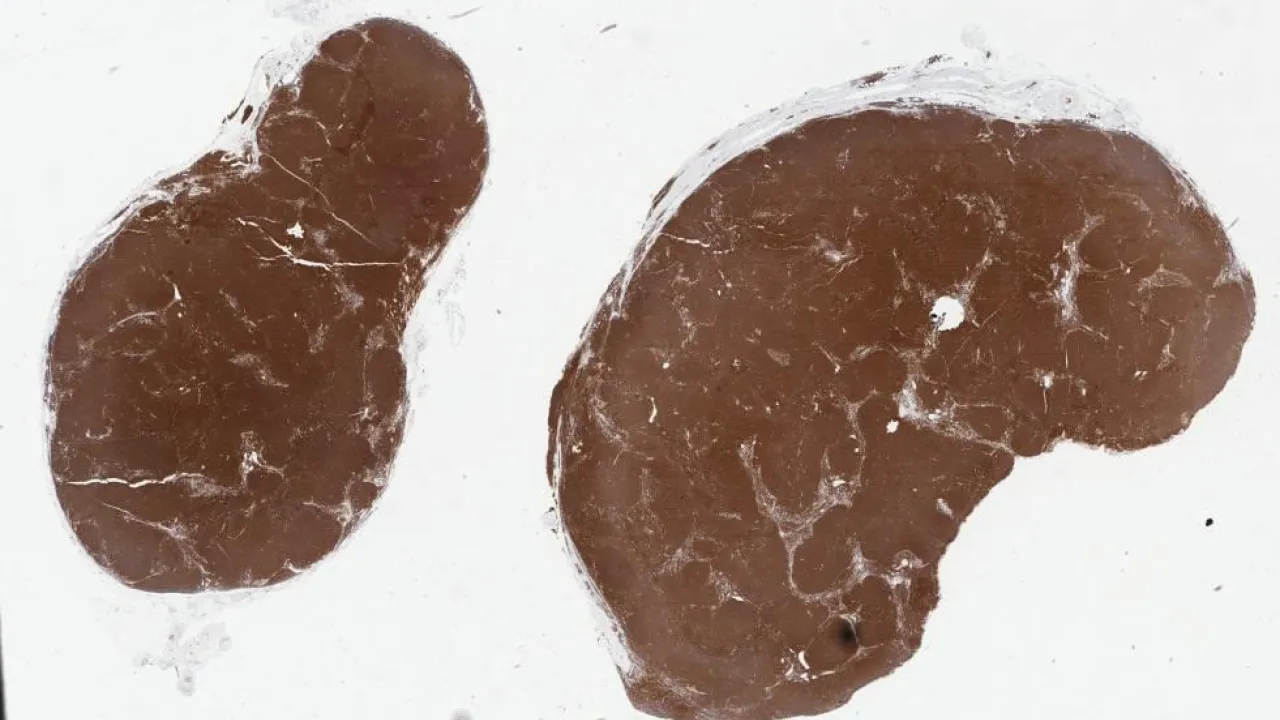

Lymph Nodes, Reactive follicular hyperplasia with progressive transformation of germinal centres